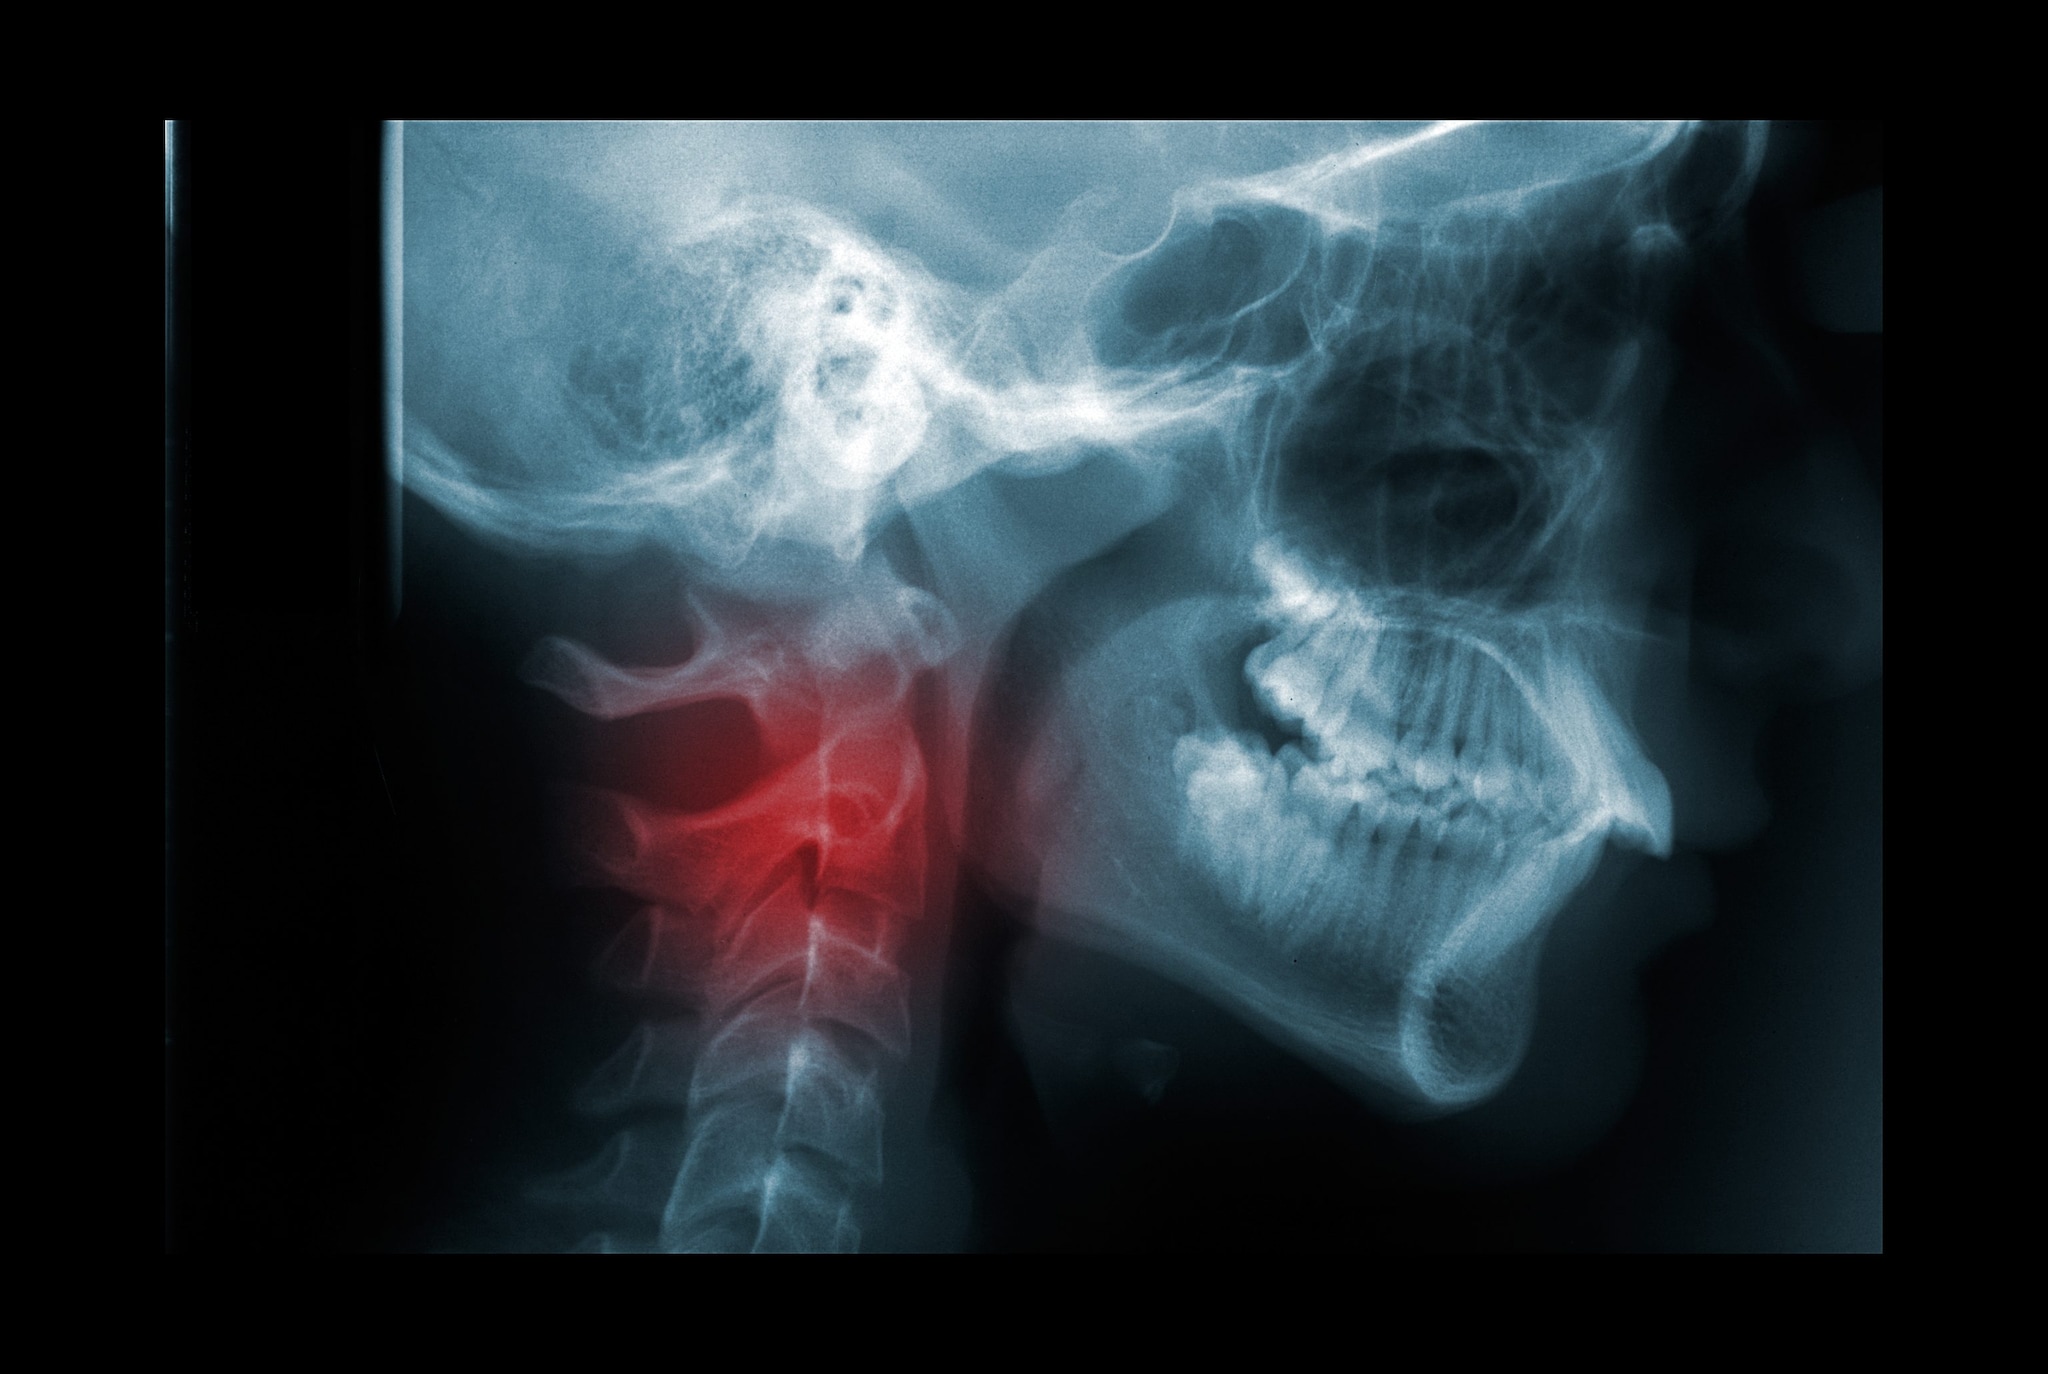

Le fratture più insidiose sono quelle cosiddette disco-legamentose, che coinvolgono sia il corpo vertebrale sia il disco intervertebrale. Sono particolarmente pericolose perché spesso non risultano evidenti nemmeno alle radiografie standard e richiedono esami più approfonditi, come la risonanza magnetica, che però non sempre viene eseguita di routine. Il rischio è che queste lesioni, nei giorni successivi al trauma, possano peggiorare e scomporsi, provocando anche la comparsa di sintomi neurologici. Tra le possibili complicanze rientrano deformità della colonna, come la cifosi, ma soprattutto deficit neurologici.

Il dolore resta il principale campanello d'allarme, soprattutto quando il paziente è cosciente e in grado di riferire i sintomi. Tuttavia devono far sospettare una lesione anche disturbi neurologici come formicolii, perdita di sensibilità, dolore irradiato o alterazioni della forza agli arti superiori o inferiori. Nei pronto soccorso esistono protocolli precisi per valutare questi traumi. Le radiografie devono includere anche il tratto cervicale inferiore e quello toracico superiore, zone che possono risultare difficili da visualizzare perché sovrapposte alle strutture delle spalle. Proprio per questo, nei casi sospetti si ricorre sempre più spesso alla TAC, un esame rapido e molto accurato, mentre la risonanza magnetica viene utilizzata quando è necessario indagare meglio i tessuti molli e le strutture nervose.